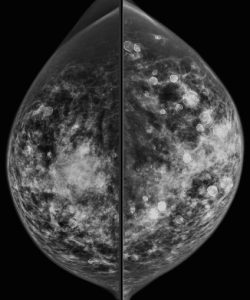

A 60-year-old woman presents for a screening mammogram:

What is responsible for the appearance of this mammogram?

C. History of direct silicone injections

Explanation: Direct injection of silicone is a method of breast augmentation that is illegal in the United States, but may still be practiced in other countries. The practice results in a mammogram with multiple high density masses (with rim calcifications) and areas of greatly increased density. Extremely dense lymph nodes may also be present. These high-density silicone breast masses make it difficult to detect a breast cancer on both physical exam and mammography.

Steatocystoma multiplex is a skin disorder, manifesting in the breast as multiple bilateral subcutaneous oil cysts. Although this patient has multiple rim calcifications (which can also occur with oil cysts), steatocystoma multiplex would not explain the presence of so many areas of greatly increased density.